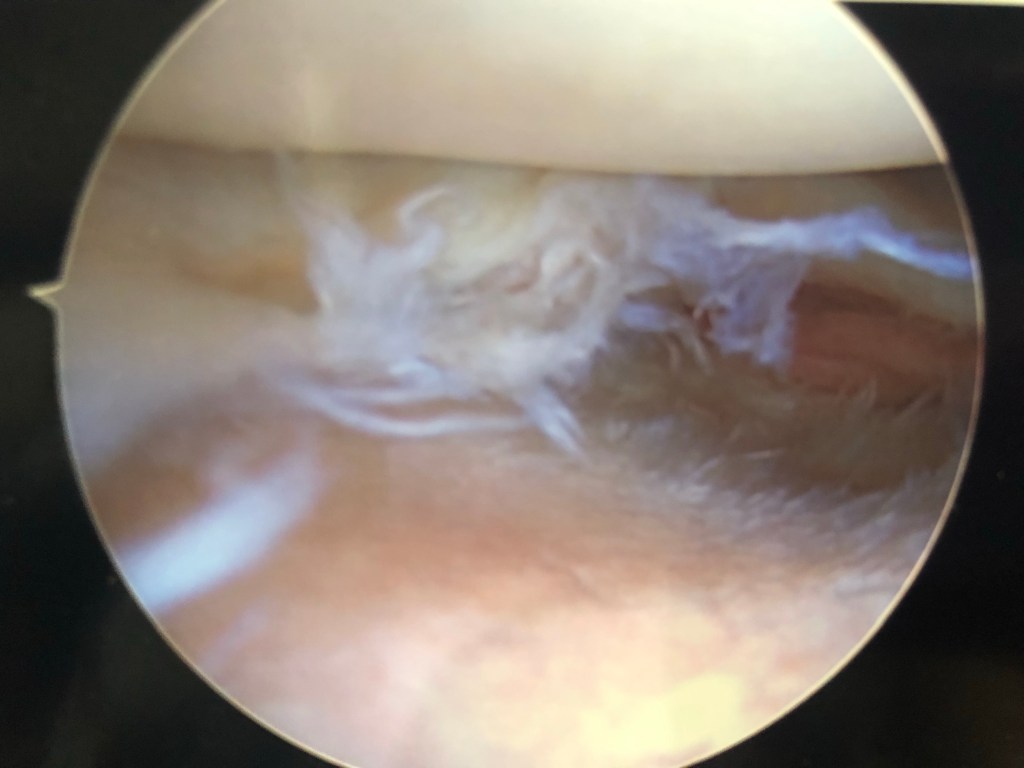

On Wednesday, I swallowed my pride and heeded my daughter’s advice to ask for help. I called my husband and admitted I was scared, afraid that I had a more serious injury than I realized. He gave me instructions to follow and although they required me to change everything about my plans for the remainder of the week, I am now on the mend. X-rays, an MRI scan and two doctors visits later, I was diagnosed with a torn- shredded really- lateral meniscus requiring arthroscopic surgery to repair. Had I not listened to my daughter and called my husband, he would have eventually seen my predicament and pointed me in this same direction, but I would still be in pain, still unable to use my right leg today, and possibly creating a worse injury for myself.